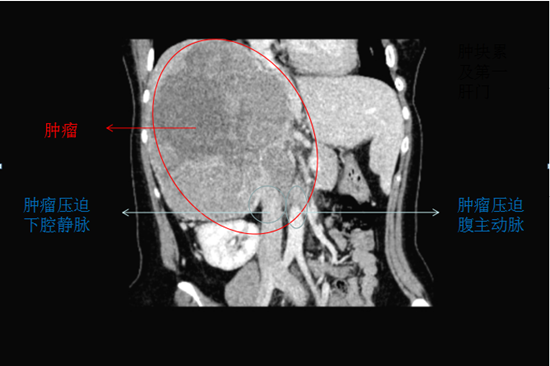

經(jīng)二次MDT多學(xué)科(血管外科、肝臟外科、內(nèi)分泌及放射科)團(tuán)隊聯(lián)合會診商討,最終決定采用同期全麻下腹腔鏡下施行MDT多學(xué)科團(tuán)隊協(xié)作下的多臟器腫瘤聯(lián)合切除手術(shù)(右腎腫塊切除+右肝后葉切除+腸粘連松解術(shù)),并制定了詳細(xì)的手術(shù)與治療方案。外科手術(shù)團(tuán)隊歷時4小時將手術(shù)順利完成,腫物大小達(dá)到 25*20*10cm3,約10斤重。

患者右側(cè)肝腎間隙巨大腫塊及肝臟轉(zhuǎn)移灶緊臨右肝靜脈、壓迫下腔兩大主要靜脈及膽管,且兩大靜脈已被腫瘤侵犯,術(shù)中稍加不小心,隨時會造成大出血。右腎、右輸尿管受壓、積水,腹腔內(nèi)失去正常的解剖結(jié)構(gòu),加上患者既往有甲亢病史及高泌乳素血癥,對手術(shù)操作、麻醉及術(shù)后管理均提出了極大的挑戰(zhàn)。

面對這個疑難病例,專家在術(shù)前規(guī)劃時先將患者的CT圖像還原成立體模型,通過賽納自主研發(fā)的WJP直噴式3D打印技術(shù)打印出來的全彩色3D打印模型,清晰地區(qū)分腫瘤與周圍重要神經(jīng)、血管的關(guān)系。